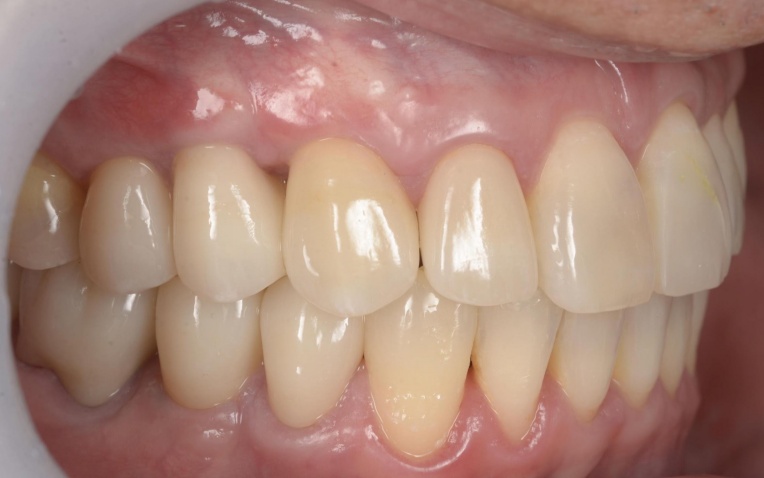

治療後

矯正治療終了後は、整えた歯並びが後戻りしないよう、細いワイヤーを固定して歯並びを安定させる装置「リテーナー」を装着しました。

その後、小樽山岡デンタルオフィスにてインプラント治療と被せ物の治療を行い、治療を終了しています。